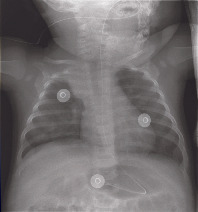

– distension avec hyperclarté des 2 champs pulmonaires, horizontalisation des côtes (plus de 9 espaces intercostaux visibles) et aplatissement des coupoles diaphragmatiques (fig. 1) ;